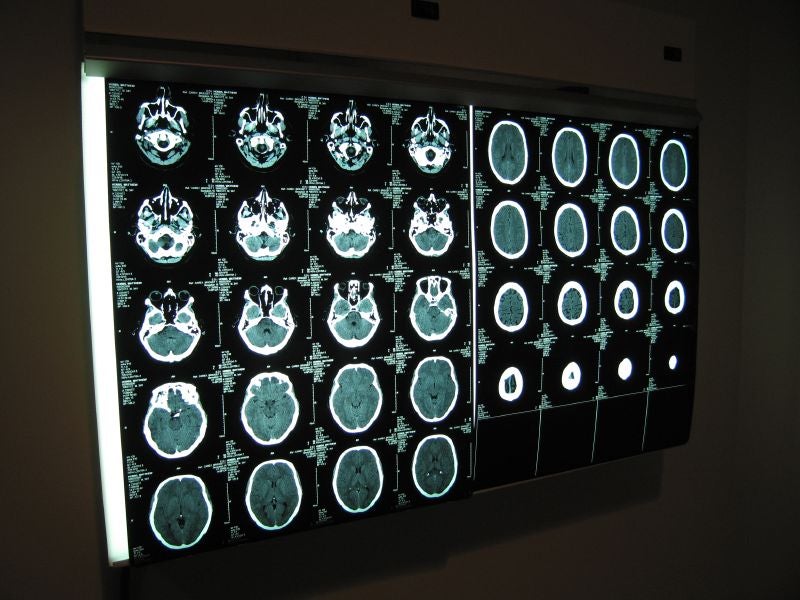

March is Brain Injury Awareness Month. Join substitute host John Munson and his guest as they discuss a subset of brain injuries that are caused by trauma. They’ll also explore the effects of traumatic brain injuries on our lives, recovery options, and how people can support someone they know with this problem.